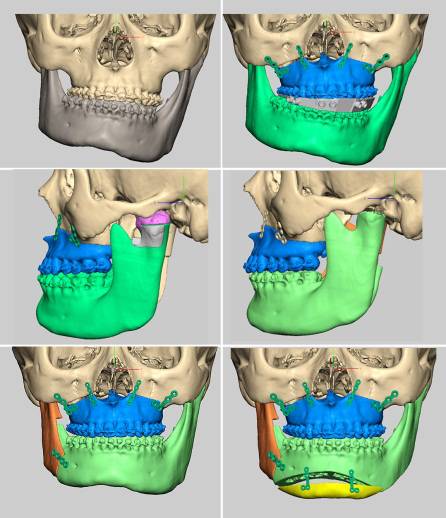

什么是计算机辅助正颌外科手术设计?

目前可使用软件将螺旋CT或锥束CT等影像学数据经计算机处理后,三维重建患者的颌骨形态,辅助牙颌面畸形的诊断,模拟手术截骨、移动、固定等,并制作相应的数字化导板辅助术中手术实施。同时因为计算机辅助手术设计可以更为直观的视察到术后颌骨的位置,更方便患者直观的了解手术效果,理解手术方案,便于医患沟通交流。

(摘自“第四章第三节 牙颌面畸形治疗计划”)

计算机辅助正颌外科手术设计